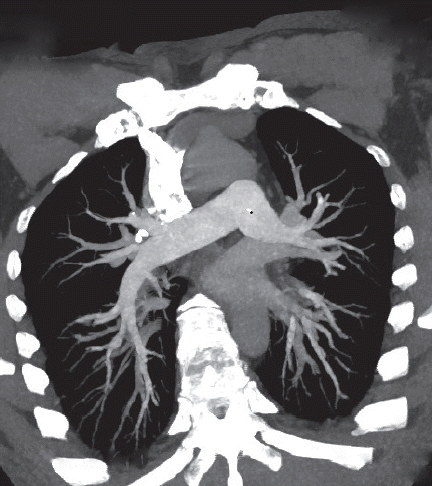

The patient underwent a CTA of the abdomen, which showed multiple deep vein thrombosis, but without definite evidence of gastrointestinal bleeding, retroperitoneal hematoma, or acute mesenteric ischemia (AMI). Gastroscopy showed hookworms in the duodenum, and the intestine is thought to be the source of bleeding (

Fig. 2Gastroscopy showing red worms swimming in the duodenum.